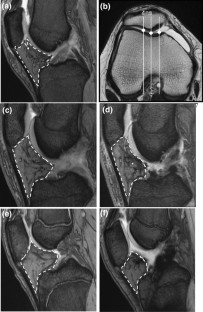

Forty-two patients who underwent primary ACLR with HT autografts were prospectively assessed for 2 years after surgery. They were randomly selected to undergo treatment with as much intercondylar IPFP preservation as possible or with intercondylar IPFP resection to confirm the ACL origin on the femoral and tibial sides, especially the femoral footprint in deep flexion of the knee joint. The total IPFP volume was calculated using sagittal MR images before and 6 months after surgery. The patients completed a subjective knee score questionnaire and were assessed for patellar tendon tenderness and pain with the half-squat test or single-leg hop test at 6 months and 2 years postoperatively.

Fig. 1